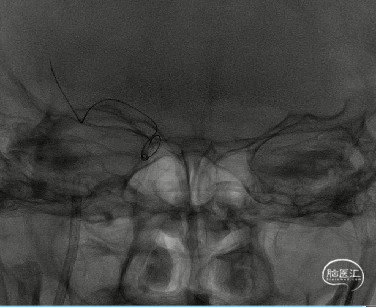

8F导引导管在多功能管及泥鳅导丝导引下直接进入右侧颈总动脉,此时Skathi远端通路导管尾端连接自制50ml负压注射器一路裸奔抽吸至C5段,反复抽吸3次,抽出大量血栓,回血通畅后,轻轻冒烟提示颈内动脉通畅,大脑中动脉M1远端闭塞,与取栓前后循环造影显示情况一致。

大脑中动脉M1段血栓采用SWIM技术-抽拉结合,避免血栓逃逸。

一次SWIM取栓,成功血管再通,达到mTICI分级:3级。